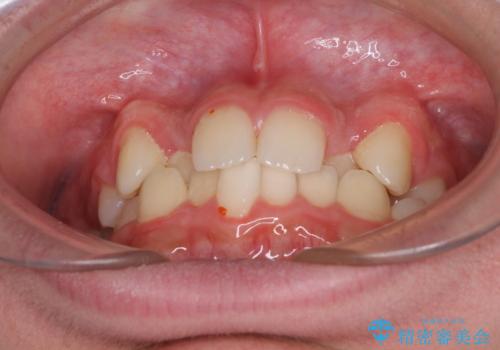

- 前歯のクロスバイトを気にして来院された患者様です。

中学生であることから、治療期間を短縮できると判断し、ワイヤー矯正にて短期間で治療を行うこととしました。

叢生のため磨き残しの多い歯列でしたが、1年弱で治療を終了でき、磨き残しや歯肉の腫れが著しく改善されました。